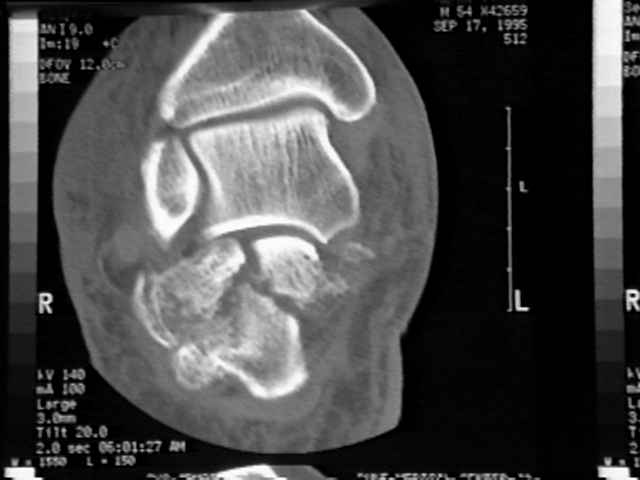

radiographs

- may show calcification within the Achilles tendon, which may indicate a more proximal tendinosis;

MRI

- may be indicated in cases of tendinosis with suspected multiple partial tears;